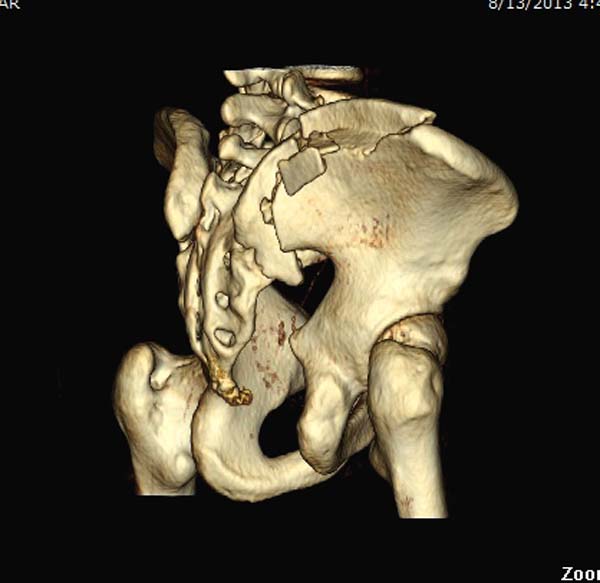

KT

1. необходима КТ таза для уточнения всех плоскостей смещения, т.к имеется не только вертикальное смещение, но и смещение кзади и ротационное

До операции желательно выставить все стандартные снимки: обзорный таза, вход + выход. А популярный у всех 3Д используется только для общего обзора, но не для детального изучения. Обычно КТ “для диагностики-стандарт, а послеоперационно - дополнительный расход”. Лучше обычные рентген-снимки, но бывают исключения, когда на снимке имеются неясности, например, винт через сакральный форамен или через сустав!